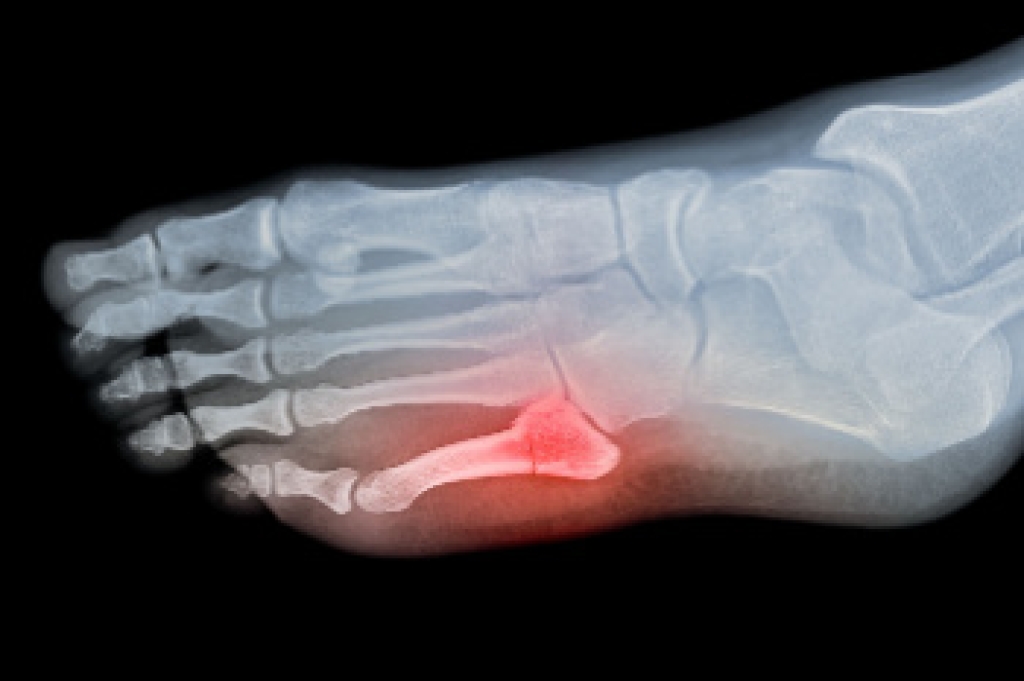

In order to diagnose your bunion, your podiatrist may ask about your medical history, symptoms, and general health. Your doctor might also order an x-ray to take a closer look at your feet. Nonsurgical treatment options include orthotics, padding, icing, changes in footwear, and medication. If nonsurgical treatments don’t alleviate your bunion pain, surgery may be necessary.